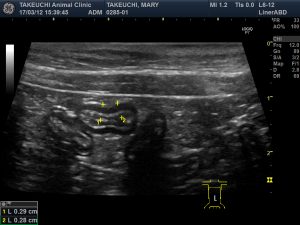

●エコー検査(超音波検査):消化管に異常な腫れや肥厚がないかを見ます。

今回、慢性下痢症に悩まされているラグドールの猫ちゃんが診察を受けにこられ超音波検査で、消化管壁の肥厚が認められた為、私が尊敬している専門医でいらっしゃる日本小動物医療センターの消化器科の「中島亘先生」に、検査をお願いしました。

中島先生の診察・検査の結果は「リンパ腫」ではなく、「IBD」でした。炎症性腸疾患、簡単に言えば「慢性腸炎(腸症)」ということでした。